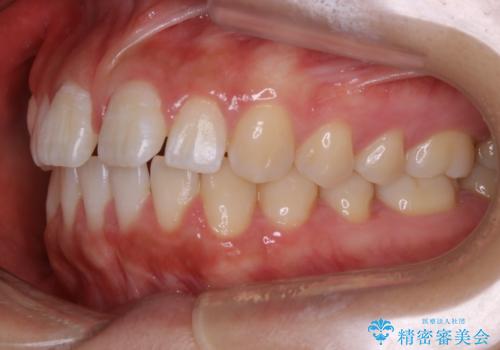

インビザライン矯正 前歯のすきっ歯を治したい

- 上顎の前歯のすきっ歯を治したいとのことで来院されました。

前歯の隙間を閉じる矯正治療の場合、インビザライン適用症例のためインビザラインによる治療をご提案しました。

後戻り防止のため、上唇小帯切除も併用しています。

上唇と歯ぐきを結ぶひも(上唇小帯)が長いと、前歯に隙間が空いてしまうことがあります。今回は隙間を確実に閉じる目的、また矯正後に再び隙間が空かないように、上唇小帯の切除も行っています。